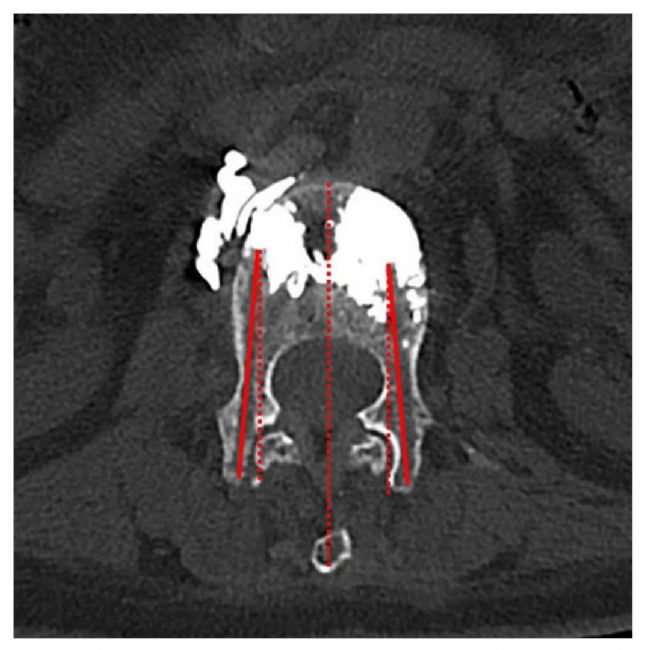

❐ 數(shù)據(jù)收集:收集了OVCF患者的基線特征,包括年齡、性別、BMDT值和椎體骨折部位。從術(shù)前、術(shù)后和術(shù)后3個月隨訪的腰椎正側(cè)位片上判斷骨水泥的彌散程度。手術(shù)過程中,記錄使用C形臂的透視次數(shù)、總輻射劑量以及是否存在骨水泥滲漏。使用VAS疼痛評分評估患者椎體骨折后的疼痛,使用ODI評分評估患者的恢復和康復情況。記錄了術(shù)前、術(shù)后3天和術(shù)后3個月的VAS和ODI評分。根據(jù)術(shù)后隨訪CT掃描中患者病椎的橫截面測量并記錄了穿針的外展角度。

① 根據(jù)術(shù)后隨訪CT的橫截面測量穿刺外展角,兩組之間存在顯著性差異(P<0.05)。